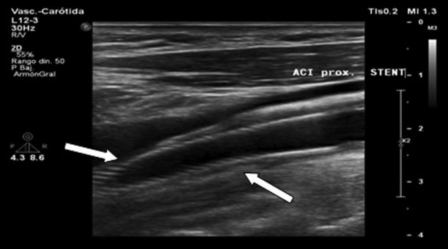

En modo B se obtiene "información morfológica." Ecográficamente el stent es hiperecogénico y puede estar posicionado desde la arteria carótida común en su porción distal o en el nacimiento inmediato de la ACI, con longitudes variables. Es importante registrar la morfología correcta de las paredes de las arterias nativas adyacentes al stent y ver la existencia de placas subyacentes en la zona de estenosis, las cuales pueden provocar una deformidad de la pared del stent y, además, la existencia de placas no cubiertas por el stent. Se debe observar la integridad del mismo y evaluar posibles rupturas (►Fig. 4).

Ecografía en modo B donde se observa stent con buena posición y aposición a la pared vascular, sin anormalidades en su calibre y luz vascular residual (Flecha).